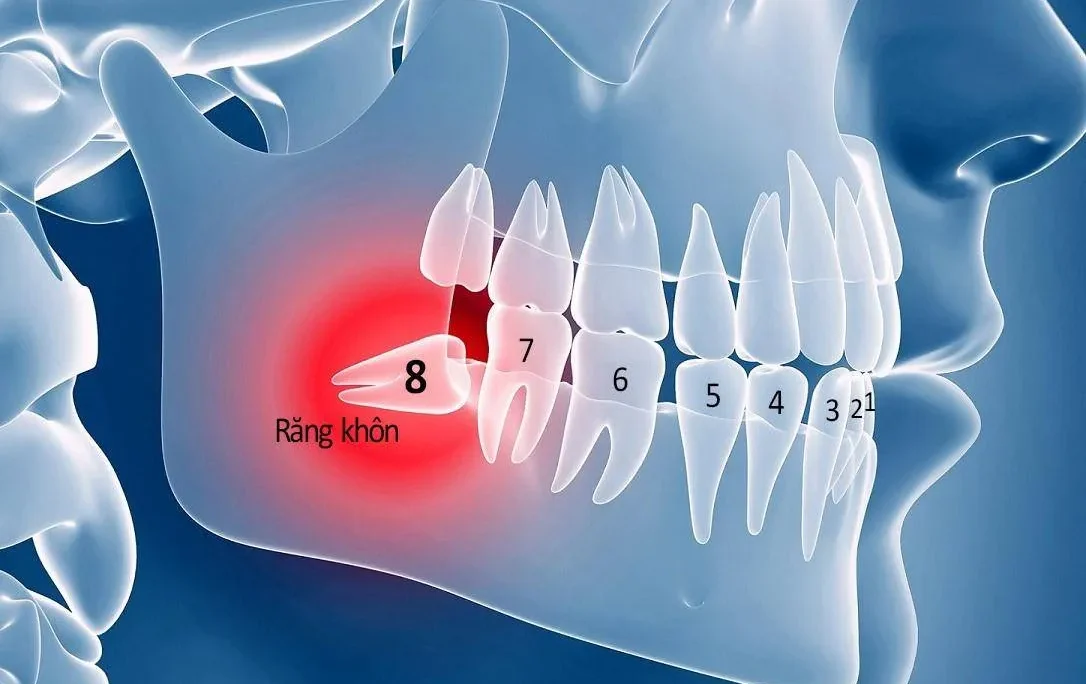

Viêm tủy răng ảnh hưởng đến phần lợi

Viêm tủy răng là một tình trạng nghiêm trọng. Nó thường xảy ra khi răng bị chấn thương dẫn đến vỡ hoặc sứt mẻ. Thông qua đó tạo điều kiện cho vi khuẩn xâm nhập vào tủy răng. Viêm nhiễm tủy răng cũng có thể xuất phát từ việc sâu răng không điều trị kịp thời. Khi vi khuẩn tấn công tủy răng, mô nướu sẽ bị sưng đỏ. Đồng thời hạch lympho sẽ nổi lên như một phản ứng bảo vệ. Viêm tủy răng có thể dẫn đến biến chứng nghiêm trọng ngoài viêm lợi trùm nổi hạch. Trong đó bao gồm mất răng và nhiễm trùng máu nếu không được điều trị đúng cách.

Các triệu chứng của viêm tủy răng bao gồm:

- Cơn đau răng dai dẳng, đặc biệt là khi ăn thức ăn quá nóng, lạnh, hoặc có vị chua, ngọt.

- Răng ê buốt khi tiếp xúc với không khí lạnh hoặc khi đánh răng.

- Nướu sưng đỏ, kèm theo sốt nhẹ hoặc cao, nổi hạch lympho.

- Hơi thở có mùi hôi, cơn đau lan rộng sang các khu vực xung quanh.